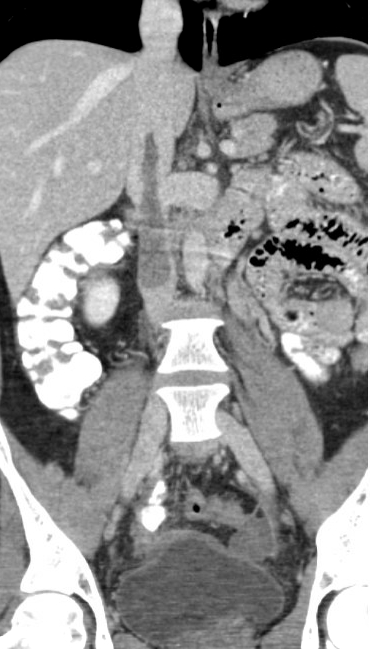

A 48-year-old female with a recent total abdominal hysterectomy for high-grade uterine stromal sarcoma presented for outpatient CT imaging to evaluate disease extent. Imaging revealed extensive IVC thrombus, a small pulmonary embolism, and a possible right atrial thrombus. The patient, who was on prophylactic-dose low molecular weight heparin (Lovenox) and had taken her morning dose, denied leg swelling or pelvic pain. Notably, she had a prior right lower extremity DVT six months earlier following an ankle fracture, treated with a three-month course of anticoagulation. She was referred to the emergency department, where transthoracic echocardiography (TTE) showed a large, mobile thrombus extending into the right atrium and ventricle. She underwent emergent mechanical thrombectomy, with complete removal of the thrombus. Post-procedure transesophageal echocardiography (TEE) confirmed no residual thrombus.